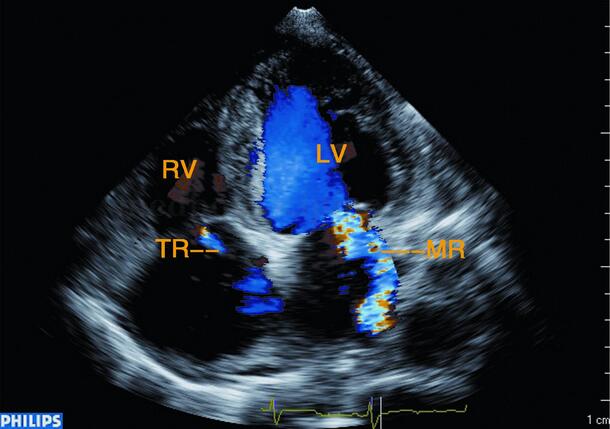

3﹒彩色多普勒 二尖瓣反流信号,彩色多普勒于左房内收缩期可见源于二尖瓣口的蓝色花彩血流束(图2‐1‐219),也可见三尖瓣及主动脉瓣口反流。

图2‐1‐219 心尖四腔心切面左、右心房内见源于二、三尖瓣口蓝色为主的花彩血流信号